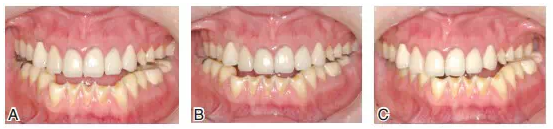

圖8患者J初診時的上頜咬合面可見舌尖明顯磨耗,橫牙合曲線呈上凸的倒曲線

圖18修復(fù)完成后的上下頜咬合面觀

圖19患者修復(fù)完成后的正面像及牙合曲線